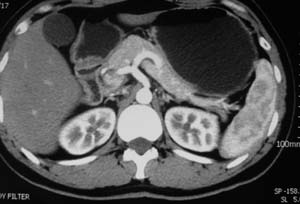

以下是引用子期在2010-3-19 20:47:00的发言:[br]血管畸形的ct增强应该有明显强化,本例并不相符合。本例双肾局部的略低密度影,累及肾盂,局部皮质明显变薄、内陷,增强扫描有轻度的强化,应考虑为炎性病变,患者为年轻男性,累及双肾的感染以结核较常见,可以没有明显的临床症状,尿中有时候也并不能查出什么;肾脓肿常有明显感染中毒症状,本例不符,另外一般的肾盂肾炎或肾小球肾炎通过小便就可确诊,其它还不能排除的是黄色肉芽肿性肾盂肾炎,然而单凭ct一般也很难鉴别。